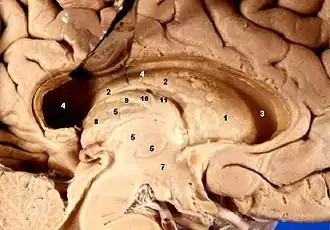

Human brain left dissected midsagittal view (Lamina affixa is #10) | |

Lamina affixa is a layer of epithelium growing on the surface of the thalamus and forming the floor of the central part of lateral ventricle, on whose medial margin is attached the choroid plexus of the lateral ventricle; it covers the superior thalamostriate vein and the superior choroid vein. The torn edge of this plexus is called the tela choroidea.[1]

On the surface of the terminal vein is a narrow white band, named the lamina affixa.